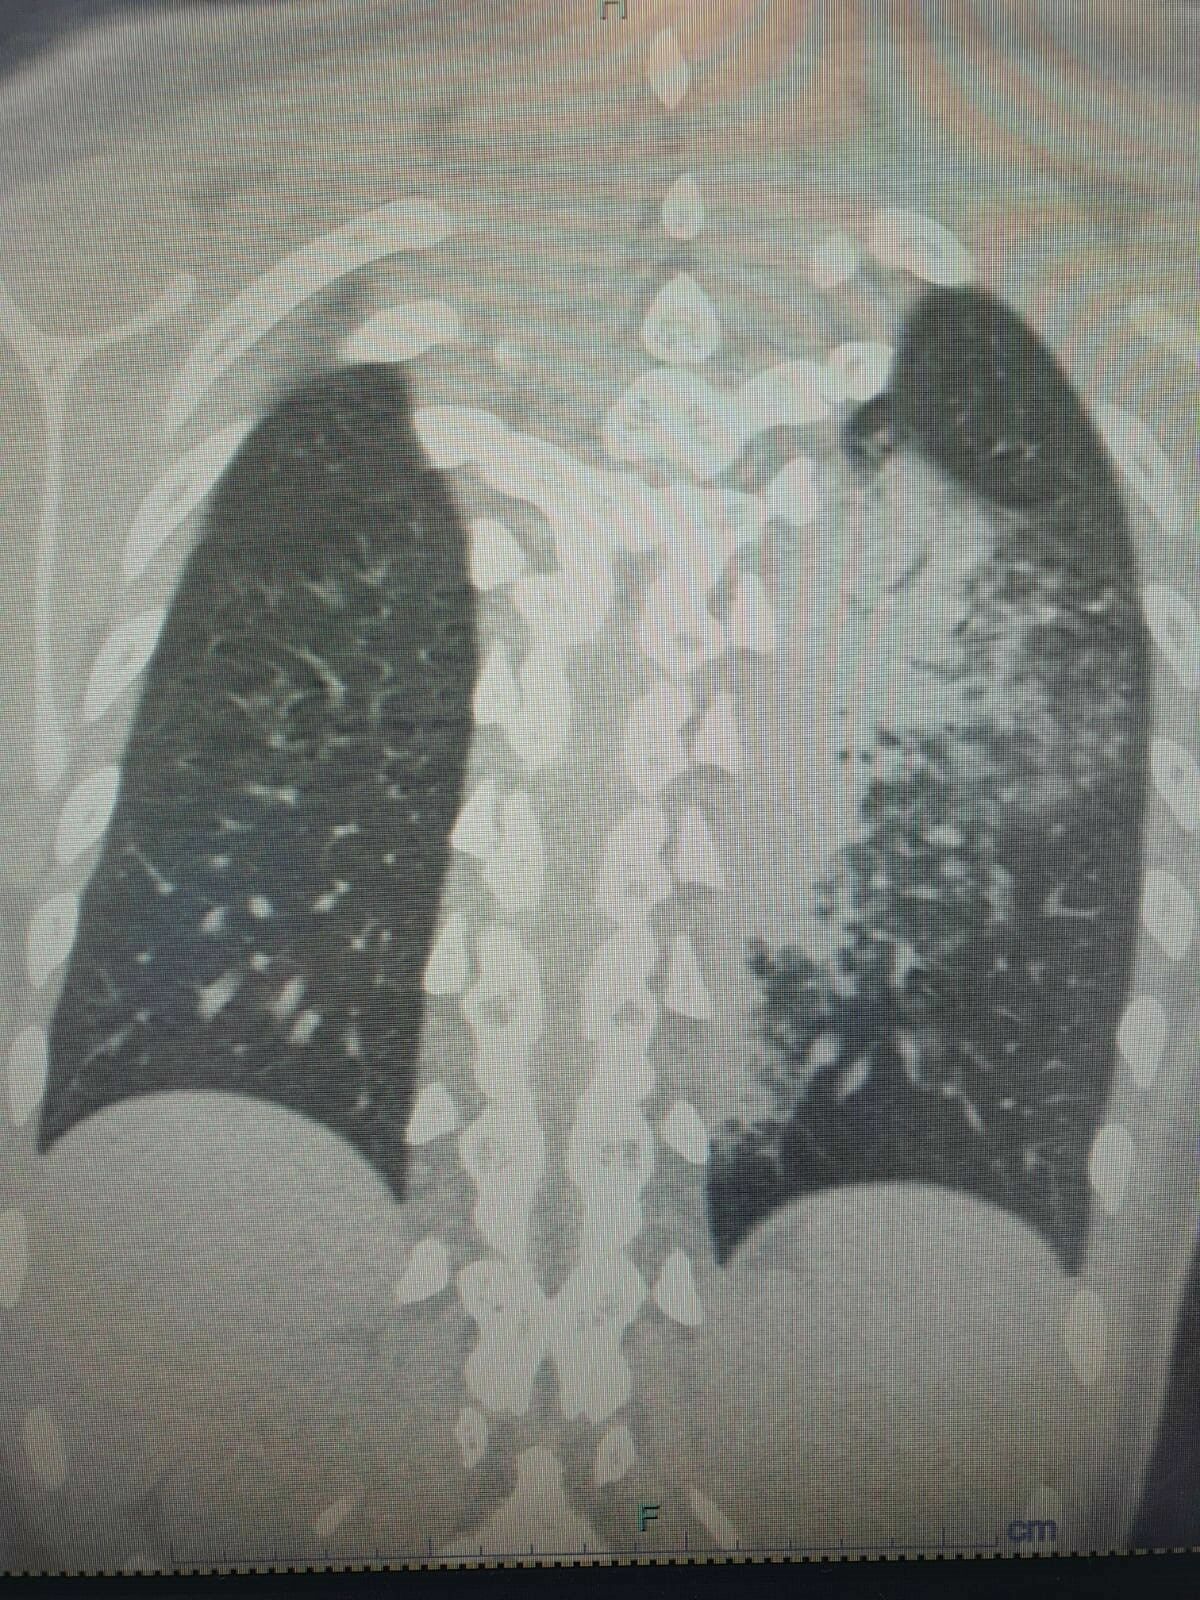

Prof. Dr. Şevket Özkaya, yaz sezonunda tatil yapanların klima kullanımının artmasıyla birlikte bronşit ve zatürre vakalarının hızla yükseldiğini belirtti. Otel ve tatil köylerinde konaklayanlar arasında 'beni klima çarptı' diyen kişilerin sayısının arttığını ve bu kişilerin çoğunda zatürre vakası tespit edildiğini söyledi. Özellikle çocuk yaş grubunun bu hastalıktan daha fazla etkilendiğini vurgulayan Özkaya, 'Ciddi sayıda, daha önce görülmemiş derecede çocuk bronşiti ve zatürresi vakaları görmeye başladık. Hatta COVID-19 salgınında, çocuk yaş grubunda bu kadar çok zatürre görmüyorduk,' dedi.

Prof. Dr. Özkaya, Legionella pneumophila isimli bakterinin klimalardan üremesi sonucu ortaya çıkan bu hastalığın, kronik rahatsızlığı olanlarda ölümcül olabileceğini belirtti. Özellikle yaşlı ve kronik hastalığı olan kişilerin klima kullanımında daha dikkatli olmaları gerektiğini hatırlattı.

Legionella bakterisinin ılık sularda kolaylıkla çoğalabildiğini ve bu nedenle sauna, hamam veya kaplıca havuzlarında dikkatli olunması gerektiğini belirten Prof. Dr. Özkaya, bakterinin su damlacıklarının solunması yoluyla insanlara bulaştığını açıkladı. 'Kontamine suların bulunduğu sıcak sulardan çıkan buhar damlacıklarının solunması ile bakteri akciğerlere ulaşır,' diyen Özkaya, klimaların iyi temizlenmesi gerektiğini ve klima zatürresinin grip belirtileriyle karışabileceğini söyledi.